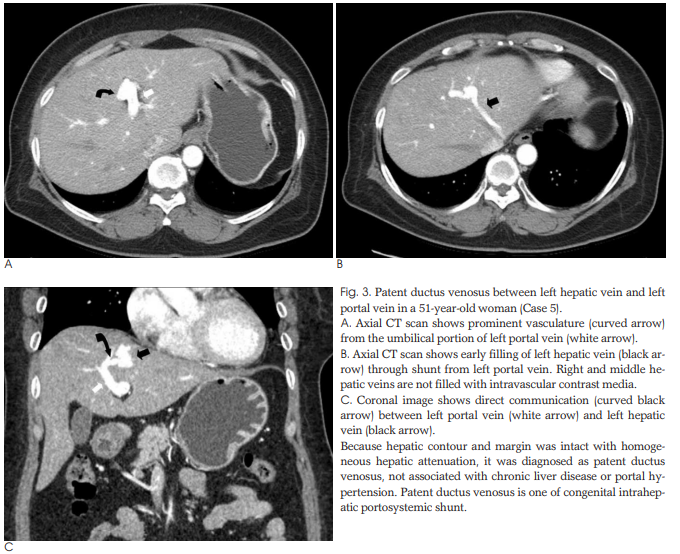

57세 여자 환자(증례 5)는 상복부 동통을 주소로 내원하였고 위내시경에서 위 폴립이 있었다. 시행한 CT에서 담석이 있었고, 좌정맥과 좌문맥 사이의 직접적인 이상단락을 보였는데 CT에서 간경화의 소견이 없고 혈액검사에서 간이상의 소견이 없어 간 이상을 동반하지 않은 정맥관잔존(patent ductus venosus)으로 진단하였다.

신생아의 4명은 초음파와 CT를 시행하였으며 성인 환자는 CT만 시행하였다. 5명 모두 좌간엽에 단락을 보였다. 신생아의 4명은 좌간엽의 원위부에 간내 문맥정맥단락이 있었고 이중 3명은 중정맥과 좌문맥(Fig. 1), 1명은 좌정맥과 좌문맥사이에 단락이 있었다. 이들 중 1명은 좌간엽에 다발성의 단락이 보였다(Fig. 2). 증례 5의 성인 환자는 좌문맥과 좌정맥이 직접 연결되는 정맥관이 남아있는 형태의 간내 문맥정맥단락을 보였다(Fig. 3).

정맥관은 태아순환의 일종으로 생후 바로 닫히기 시작하여 15-20일경에 완전히 닫힌다. 좌문맥과 좌정맥 혹은 하대정맥 사이의 태아순환으로 간혹 성인에서 보고되고 있다.